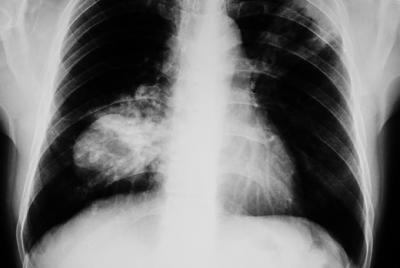

Lung Cancer, Lung cancer types, Non-small cell Lung cancer, Small cell Lung cancer, Lung cancer symptoms, Lung cancer causes, Risk factors that increase the chances of developing Lung cancer, Smoking and Lung cancer, Complications of Lung cancer, Lung cancer diagnosis, Lung cancer stages, Non-Small cell Lung cancer stages, NSCLC, Small cell Lung cancer stages SCLC, Lung cancer treatment, Small cell lung cancer, SCLC, treatment, Non - small cell lung cancer, NCLC, treatment, Surgical treatment of Lung cancer, Lung cancer drug therapy, Ways to prevent lung cancer.